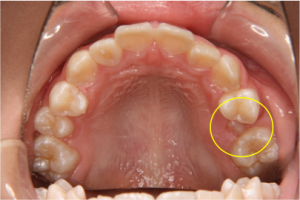

●埋伏歯の治療

(図9, 図8レントゲンの口腔内写真。右上犬歯が埋伏して隣の前歯(側切歯)が保存できず抜歯後、開窓術を行い犬歯の牽引開始したところ)